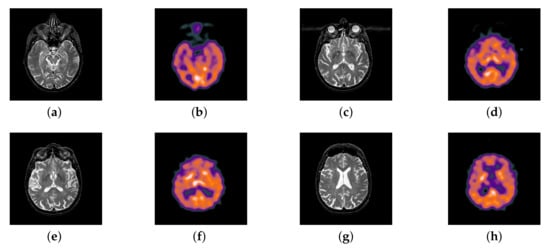

In this section, all FDG images are derived from the normal human brain, but the angle is chosen differently in Figure 24. In Figure 25, Figure 26, Figure 27 and Figure 28, we find that the color information obtained by the image fusion method based on NSCT, DTCWT, and LPSR is better preserved, but the structure information is lost more. The fusion image based on GFF, IGM, and FusionCNN method retains the complete structure information in the MRI image, but the color obtained from the FDG image is distorted. The image color information obtained by DDcGAN fusion method is too bright, resulting in unclear color area details and low contrast of color region. In contrast, the image obtained by our algorithm has moderate brightness of color information, complete structure information, and complete biological detail information.

Figure 24.

Four pairs of MRI-Fludeoxyglucose (FDG) source images: (a,c,e,g) are MRI images; (b,d,f,h) are FDG images.

Figure 25.

Fused medical images obtained by different algorithms (Figure 24a,b): (a) DTCWT, (b) GFF, (c) NSCT, (d) LPSR, (e) IGM, (f) FusionCNN, (g) DDcGAN, and (h) FusionNet.

Figure 26.

Fused medical images obtained by different algorithms (Figure 24c,d): (a) DTCWT, (b) GFF, (c) NSCT, (d) LPSR, (e) IGM, (f) FusionCNN, (g) DDcGAN, and (h) FusionNet.

Figure 27.

Fused medical images obtained by different algorithms (Figure 24e,f): (a) DTCWT, (b) GFF, (c) NSCT, (d) LPSR, (e) IGM, (f) FusionCNN, (g) DDcGAN, and (h) FusionNet.

Figure 28.

Fused medical images obtained by different algorithms (Figure 24g,h): (a) DTCWT, (b) GFF, (c) NSCT, (d) LPSR, (e) IGM, (f) FusionCNN, (g) DDcGAN, and (h) FusionNet.

The averaged subjective scores of MRI-FDG fused images obtained by 8 algorithms are shown in Figure 29 and Figure 30, and objective evaluation indicators are all shown from Figure 31, Figure 32, Figure 33, Figure 34, Figure 35, Figure 36, Figure 37, Figure 38, Figure 39 and Figure 40. Overall, our algorithm performs well in EN, FMI, RMSE, AG, SSIM, , , and . Our algorithm is the best of eight algorithms in the fusion of image structure information. In the metric of cross entropy and visual information fidelity, our algorithm is slightly inferior to other algorithms. However, from the overall evaluation, the algorithm has obvious advantages in fusion MRI and FDG.